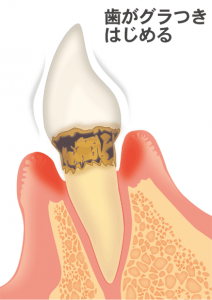

歯周病が進むとどうなるか

■歯がグラグラして抜けてしまう

例え抜けなくても…

■以前より細菌が付着しやすくなる上に、付着した細菌を物理的に除去するのが難しくなるので、口腔内の細菌レベルが高くなる